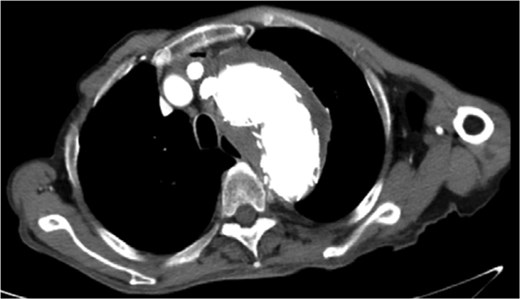

Despite recovery, the patient remained physically exhausted and required ongoing rehabilitation. In May 2023, after a COVID-19 infection, the patient experienced blood in phlegm. CTA confirmed successful aneurysm repair with no endoleak (Fig. 3). Thus the patient was hospitalized in the respiratory department. Relevant pulmonary examination indicators and lung CT results revealed no lung lesions associated with blood in sputum (Fig. 4). However, throughout July, 2023, intermittent blood in phlegm continued, and a CTA on July 19, 2023, revealed a type IV endoleak (Fig. 5). Conversely, aortography on July 27, 2023, showed no obvious endoleak. Closed drainage of the left thoracic cavity was performed, but blood in phlegm recurred on August 9, 2023. A Gore C-TAG stent graft was deployed in the thoracic aortic arch, with its proximal end anchored at the ostium of the left subclavian artery stent graft to ensure complete coverage of the endoleak site both proximally and distally(Fig. 6). Post-surgery, blood in phlegm symptoms abated.

Lung CT results revealed no lung lesions associated with blood in sputum.